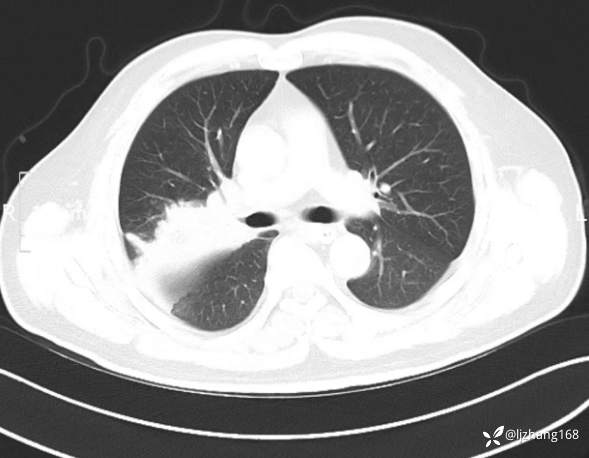

中年男患,右肺团片影,炎症0R肿瘤?

辅助检查:糖化血红蛋白12.3%。肺炎支原体IgG、IgM、呼吸道合胞病毒均未见明显异常。胸部CT:右肺上叶阻塞性肺炎。